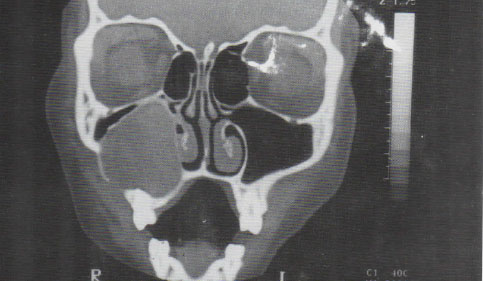

Um adolescente de 15 anos com expansão do palato, resultante de um ameloblastoma no maxilar.

Imagem tomográfica computadorizada da mesma paciente observada na figura acima que

mostra um ameloblastoma que quase preencheu o seio maxilar e tinha invadido a cavidade nasal.

As tábuas ósseas corticais palatina e vestibular estavam expandidas, havendo perfuração da tábua vestibular em uma área.ODONTOMA: